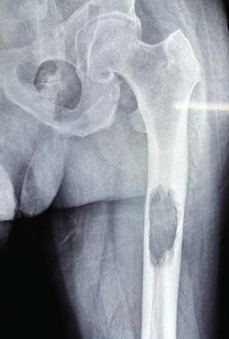

The Importance of Closed Reduction and Internal Fixation done with Intramedullary Implants in Pathological Fractures – A Case Series

Kapil Bansal , Anshul Dahuja , Iqbalpreet Singh , Krishmveer Singh , Manmohan Singh , Rahul Garg ………………………………p.335-342